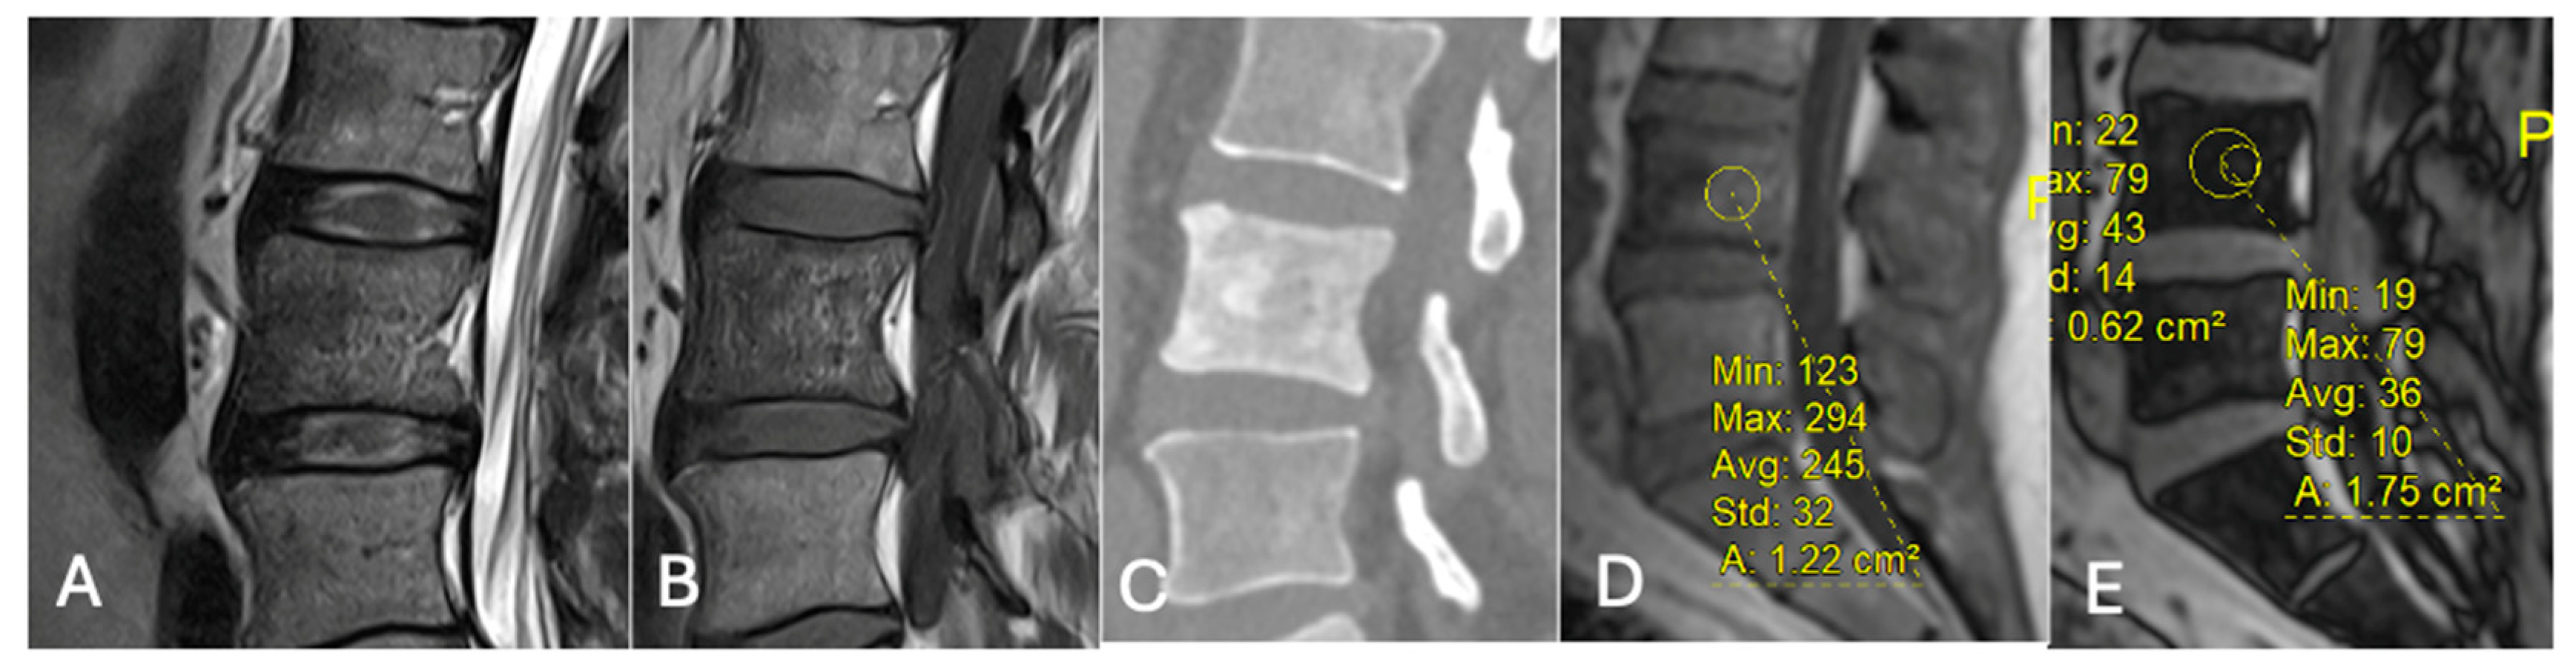

Figure 17.

Aggressive sacral haemangioma with soft tissue mass. Out-of-phase, in-phase, and STIR sagittal MRI spine as labelled on images (bottom left), showcasing the expansile nature of the lesion but also the internal fat content as demonstrated by >20% signal dropout of signal intensity values (55 SI vs. 184 SI) on the out-of-phase vs. in-phase sequence.

Figure 21. Focal marrow hyperplasia in L4. Sagittal T1 (A), T2 (B), CT (C), and chemical shift (D,E), showing heterogeneous signal on T1 and T2 and sclerosis on CT with significant signal drop on chemical shift images (D,E). - Characterising Indeterminate Marrow Lesions: In patients with cancer, incidental marrow lesions often cause clinical concern. CSI helps identify those lesions with retained fat, reducing the need for biopsy or further imaging such as bone scan or positron emission tomography (PET) [39] (Figure 18).

Using a 20% signal drop-off threshold on chemical shift imaging (CSI), Davies et al. [39] observed a sensitivity of 91.7% and a specificity of 72.7% for distinguishing benign from malignant bone lesions. This suggests that while lesions with ≤20% signal loss should be considered indeterminate due to limited specificity, CSI can confidently exclude malignancy when signal drop exceeds 20%, given its high negative predictive value (97.1%). Accordingly, biopsy may be avoidable in lesions with >20% signal drop, whereas histological confirmation or follow-up remains advisable for indeterminate cases (Figure 17, Figure 18, Figure 19 and Figure 20).